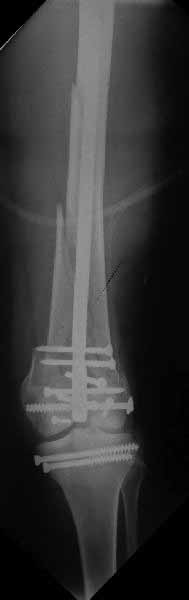

В приложении пример недавней операции, C3, открытая репозиция, фиксация мыщелков спицами и винтами, ретроградный синтез большеберцовым гвоздем 10,5 мм диаметром, винты 5 мм.

Позволю себе напомнить коллегам ещё раз, что являюсь сторонником антеградного остеосинтеза при переломах дистального эпиметафиза бедренной кости. Такая приверженность основана не на преимуществах внесуставного введения стержня или большем проценте положительных результатов. Она основана на возможности обеспечить блокирование на минимальном расстоянии от суставной поверхности в нескомпрометированной кости и, таким образом стабилизировать максимально низкие переломы. В приведенном Вами случае самый дистальный из блокирующих винтов проведен на расстоянии более 2 см от конца стержня. Из-за того, что к стержню присоединяется кондуктор, на стержне теряется 1-1,5 см его длины, где можно было разместить отверстия для блокирования. И что более важно, вместе с потерянной для этой цели длиной стержня утрачивается для размещения блокировочных винтов, пожалуй, самая ценная часть дистального эпиметафиза бедренной кости. Проблемы дистального блокирования в разных плоскостях, локализации точки ввода стержня при антеградном остеосинтезе – это всё решаемые технические проблемы. Но антеградный остеосинтез низких дистальных переломов бедра при адекватном блокировании в нескомпрометированной кости обеспечивает решение стратегической задачи – стабильный остеосинтез и возможность нагрузки.

На этом большеберцовом стержне центр ближайшего к кондуктору отверстия в 14 мм от конца. И пример был про то, что пластина тут, скорее всего, была бы не худшим выбором.